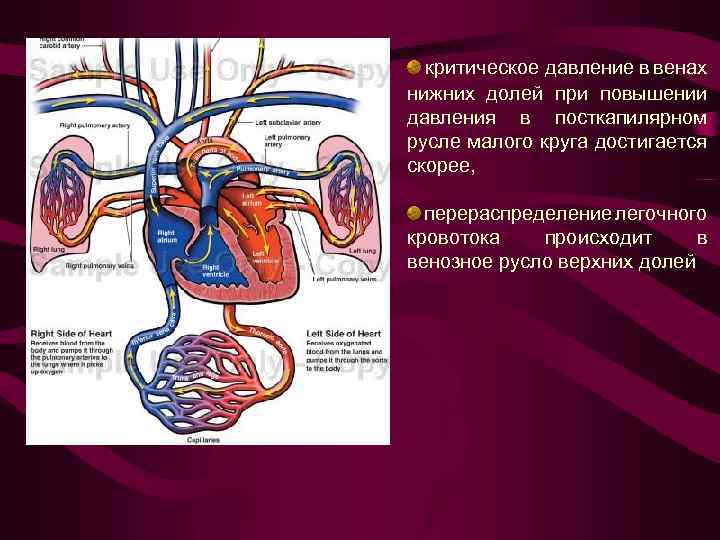

критическое давление в венах нижних долей при повышении давления в посткапилярном русле малого круга достигается скорее, перераспределение легочного кровотока происходит в венозное русло верхних долей

критическое давление в венах нижних долей при повышении давления в посткапилярном русле малого круга достигается скорее, перераспределение легочного кровотока происходит в венозное русло верхних долей

Схема перераспределения легочного кровотока при левожелудочковой недостаточности Сократительная слабость ЛЖ ↑ давления в ЛП до 15 мм рт. ст. Резкое замедление кровотока в посткапилярном звене малого круга Сужение просвета посткапилярного русла в базальных отделах Кровоток перемещается в верхние сегменты- Цефализация 1 ст. - верхнедолевой венозный застой (инверсия легочного кровотока)

Схема перераспределения легочного кровотока при левожелудочковой недостаточности Сократительная слабость ЛЖ ↑ давления в ЛП до 15 мм рт. ст. Резкое замедление кровотока в посткапилярном звене малого круга Сужение просвета посткапилярного русла в базальных отделах Кровоток перемещается в верхние сегменты- Цефализация 1 ст. - верхнедолевой венозный застой (инверсия легочного кровотока)

1 -верхнедолевой Усилен легочный рисунок в венозный застой верхних долях, укрупнен колибр (инверсия верхнедолевых вен. легочного Корни легких обычной величины, кровотока) но может отмечаться его незначительное расширение и увеличение колибра ортогональных теней сосудов в центральных отделах корня. Среднее давление в левом предсердии от 10 до 15 мм рт. ст.

1 -верхнедолевой Усилен легочный рисунок в венозный застой верхних долях, укрупнен колибр (инверсия верхнедолевых вен. легочного Корни легких обычной величины, кровотока) но может отмечаться его незначительное расширение и увеличение колибра ортогональных теней сосудов в центральных отделах корня. Среднее давление в левом предсердии от 10 до 15 мм рт. ст.